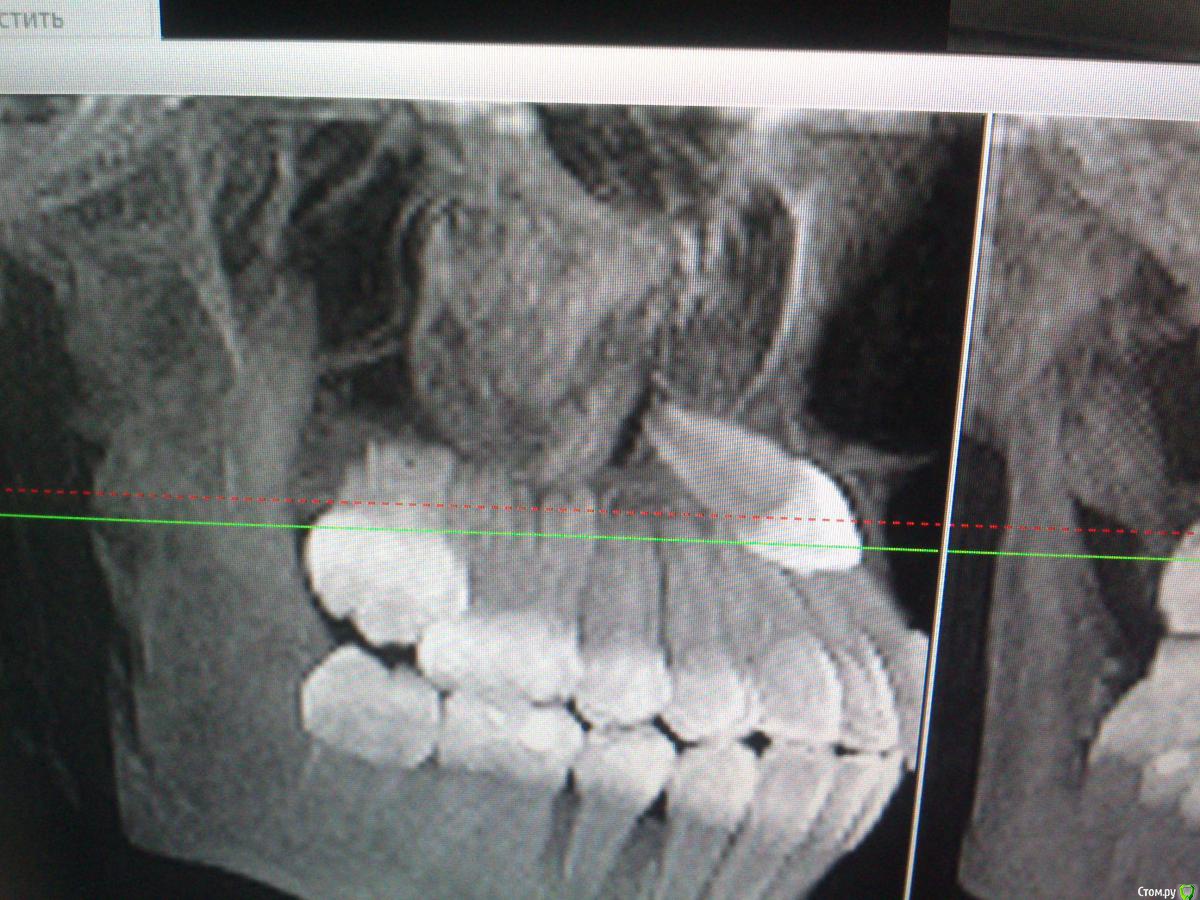

GoDemon Опубликовано 1 мая, 2015 Поделиться Опубликовано 1 мая, 2015 Здравствуйте, коллеги! Доктор - ортодонт дала данные клкт пациентки (10 лет), которой планируется ортодонтическое вытяжение клыка. От меня требовалось создать доступ. Но возник вопрос, что за тень- образование в области коронки клыка ??? думал, что, возможно, фолликулярная киста, но зуб полностью сформирован, хотя видно, что корни 2.1 и 2.2 расходятся( то ли клык их раздвинул, то ли образование вокруг него так их смещает). Так что уверенности на счет фолликулярной кисты нет, может просто остатки фолликула??? Хотелось бы услышать ваше мнение по поводу диагноза и тактику при раскрытии зуба ( если это окажется возможным делать) - просто создать доступ или все там хорошенько вычистить при раскрытии??? Спасибо. Ссылка на комментарий

natan. Опубликовано 21 мая, 2015 Поделиться Опубликовано 21 мая, 2015 если радиус радиолюцентного образов-я видимого на снимке меньше 3- 4 мм то некоторые авторы считают что это enlarged follicle Ссылка на комментарий